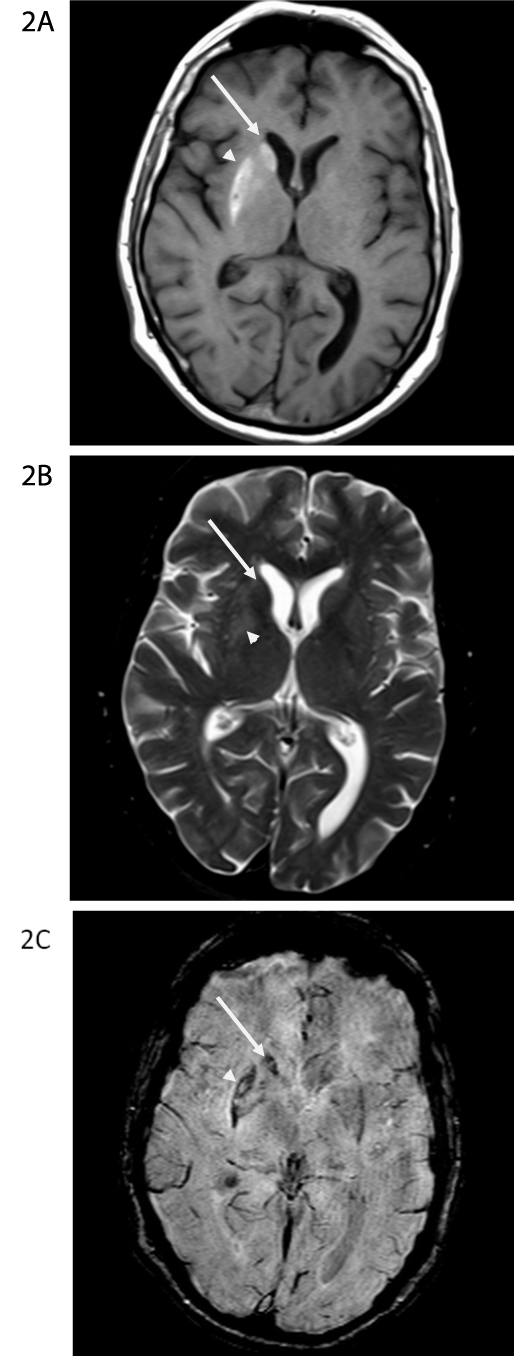

Figure 2A-C: MR scan obtained the day after the CT scan in Figure 1. On the

non-contrast T1-weighted image at the level of the basal ganglia (Figure 2A),

there is T1-shortening (hyperintensity) within the right caudate nucleus head

(long arrow) and putamen, greatest along the lateral aspect (arrowhead). On

the axial T2-weighted image at the same level (Figure 2B), there is subtle

hyperintensity in the putamen (arrowhead). The caudate head has essentially

normal signal (long arrow). On the susceptibility weighted image (Figure 2C),

there is susceptibility artifact in the right caudate nucleus head (long arrow)

and lateral aspect of the right putamen (arrowhead), similar in distribution to

the signal abnormality on the T1-weighted images and the increased density

on the CT scan.

Unenhanced CT head revealed increased density in the head of right caudate nucleus and subtle increased density in the lateral aspect of the right putamen. The right lentiform nucleus appeared smaller than the left. Contrast enhanced brain MRI revealed T1 shortening (hyperintensity) within the head of the right caudate nucleus and putamen, which was more pronounced along the lateral aspect. The axial T2-weighted image revealed subtle hyper intensity in the putamen while the caudate head had a normal signal. Vascular imaging was unremarkable. His hemoglobin A1C was 12.7 % and plasma osmolality was 301mOsm/kg (checked after he was hydrated in the emergency department). The provisional diagnosis was HBHC due to non-ketotic hyperosmolar hyperglycemia.